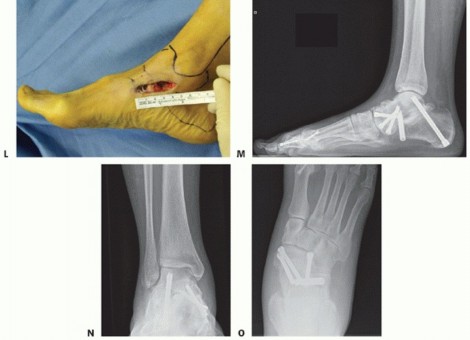

Correct the deformity first by reducing the former talonavicular joint, making sure to correct the frontal plane position of the navicular (eg, to achieve full correction of any forefoot supination deformity) (TECH FIG 13H-L).

Stable fixation is achieved by triple screw fixation at the talonavicular and double-screw fixation at the subtalar joint (TECH FIG 13M-O).

TECH FIG 13 • (continued) H. The Kirschner wires in the navicular and talar bones are kept in place and serve to reduce the talonavicular joint properly. I. Frontal view showing the frontal realignment at the talonavicular joint using both Kirschner wires as joysticks. J. A first guiding Kirschner wire is inserted through the tuberosity of the navicular into the talus. Two further guidewires will be used to properly stabilize the talonavicular joint in the frontal plane. K. After inserting two additional guidewires from the bottom through the subtalar joint, fluoroscopy is used to insert the cannulated screws (QWIX, Integra Lifesciences, Plainsboro, NJ). L. The deltoid ligament is reattached to the spring ligament using nonabsorbable sutures. The foot looks properly positioned at the end of surgery. Note the short incision

that is used for this procedure. At 2 months, weight-bearing radiographs are obtained. M. Lateral view. N. AP view of the ankle. O. AP view of the foot.